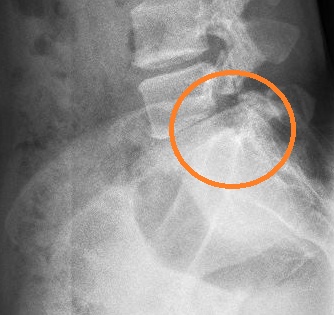

杨女士,30 岁,因长期久坐且健身方式不当(频繁进行硬拉锻炼),两年前开始出现腰痛和左腿痛。当时于我院脊柱外科蒋帅副主任医师处就诊,诊断为“腰椎间盘突出症、腰5峡部裂”,症状较轻,采取保守治疗后有所好转,但腰痛仍时有反复且逐渐加重。上个月劳累后,左腿出现放射状疼痛,输液治疗后虽有缓解,但左腿麻木严重。再次就诊后,腰椎磁共振显示椎间盘脱出并向下游离,CT显示L5椎弓根峡部断裂,X片提示腰椎不稳,经详细检查,确诊为:L4/5 巨大腰椎间盘脱出和L5 双侧腰椎峡部裂。

这两种疾病同时存在,使她的腰痛和腿痛症状雪上加霜,患者L4/5巨大的腰椎间盘脱出严重压迫了神经根,需手术干预,否则神经受压时间过长会造成更严重的神经损伤。患者腰椎峡部裂导致腰椎不稳,腰5/骶1的椎间盘变性,腰痛逐年加重,也需手术处理,否则病情会逐渐加重。